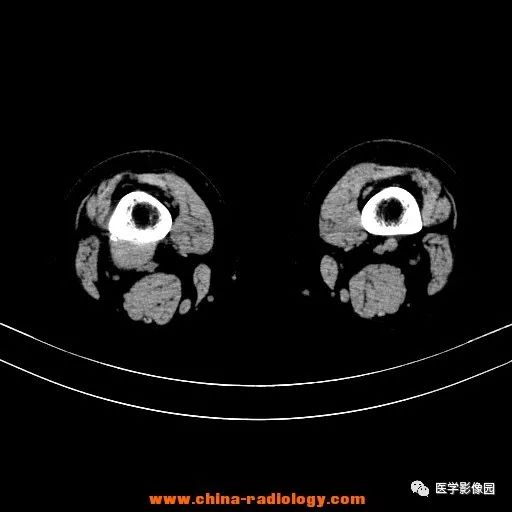

患者女性,29岁,右膝关节痛疼3月余,局部无红肿。

影像学表现:右股骨远端外后方可见局限性骨质破坏及软组织肿块,边界清楚。

病理结果:梭形细胞瘤